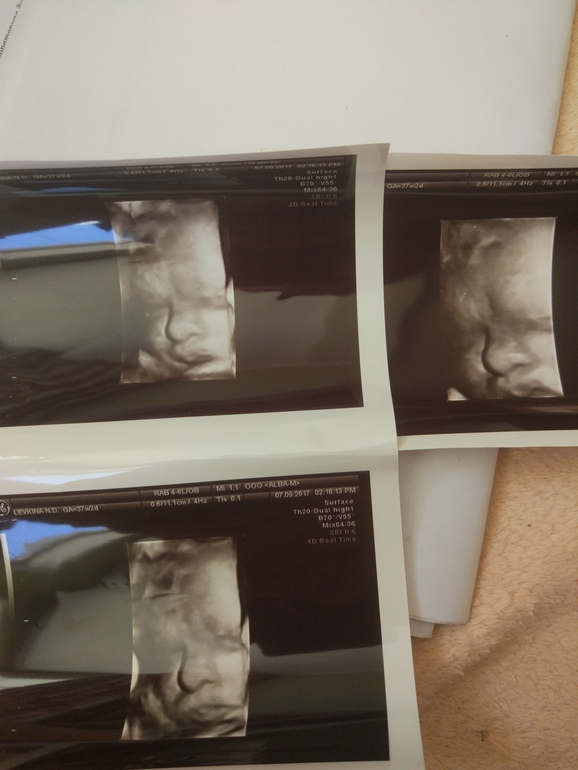

Врач в Артёме очень понравилась. Ребёнок очень хорошо ощущается. Чувствую пяточки отчётливо) Сегодняшнее узи по параметрам показало 35-36 недель, т.е. Отставать стал на неделю. Но узист заверил, что это не задержка, а просто он маленький =) Конечно.. Мама 163, папа 168. Посмотрим, узи сильно привирает. Плацента поднялась прилично, выше головы уже, ура.

Узи в 30 недель:

Фото в 37